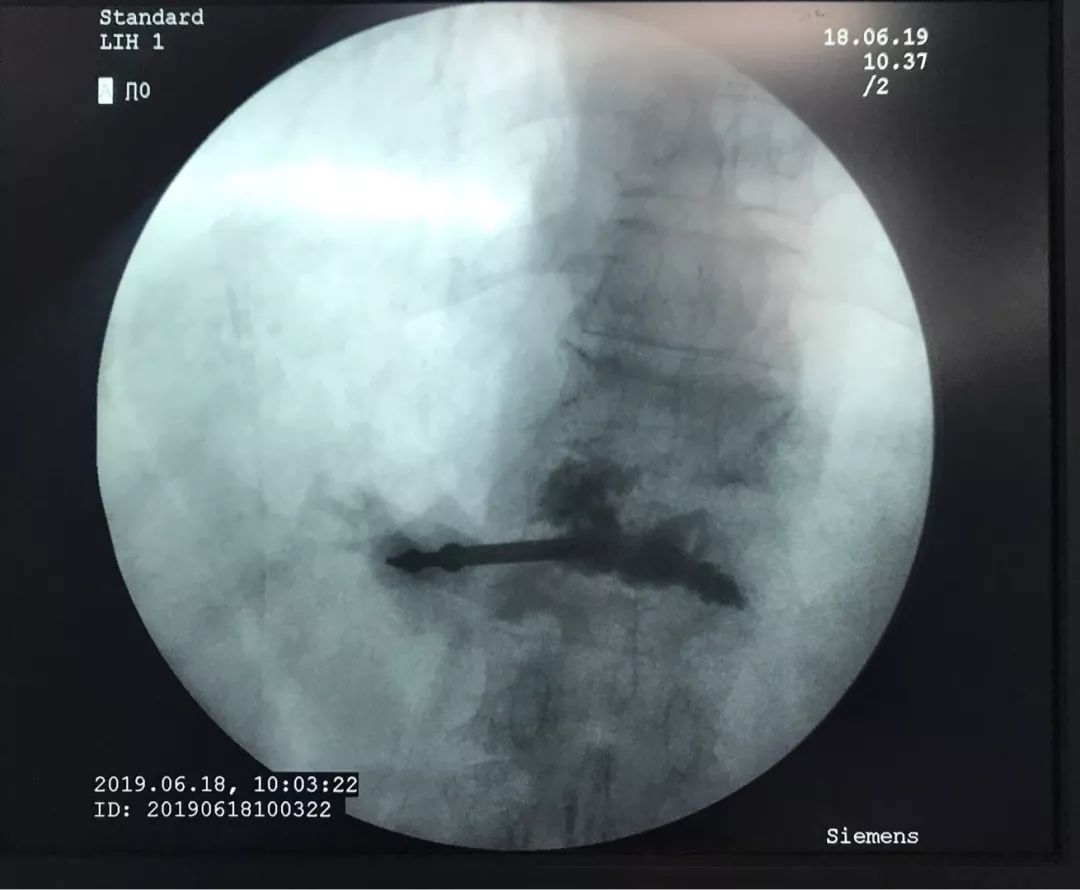

骨水泥灌注术中

术中椎体穿刺时,椎体密度显著下降,穿刺阻力显著降低,引流暗褐色血性液体,送病理检测。